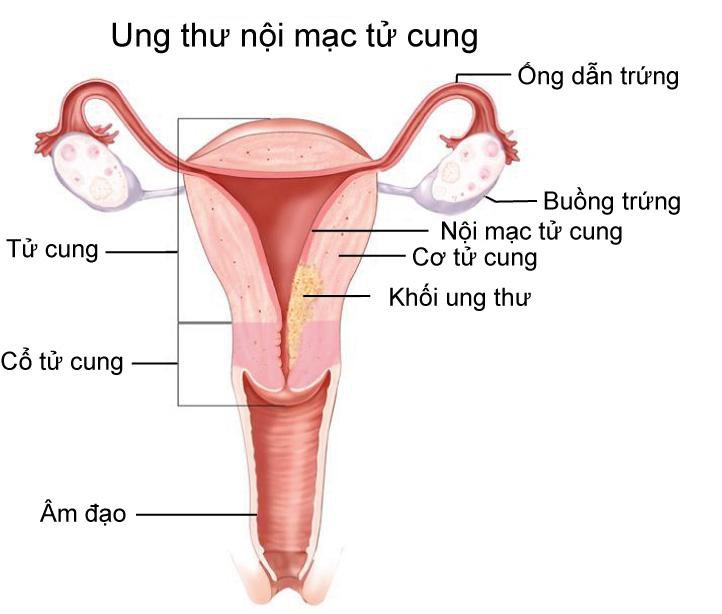

- Siêu âm đầu dò âm đạo là gì? Vai trò của siêu âm đầu dò trong chẩn đoán bệnh lý phụ khoa

- Tử cung đôi là như thế nào? Tử cung đôi có thể gặp có vấn đề gì?